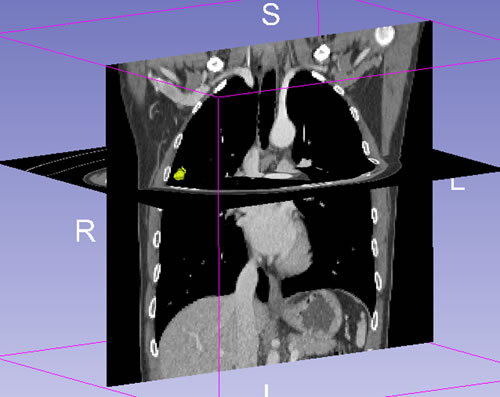

Figure 3: Example of CT images showing segmentation of lung tumor. Semiautomatic tumor segmentation was done on every slice of the tumor using 3D slicer (a), and the 3D view of the segmented tumor (b) which was shown in yellow.

CT image analysis and post-processing

Two radiologists (with 6, and 3 years’ experience in thoracic CT imaging, respectively), who were blinded to clinical and histiopathological data, reviewed all CT images separately. They were asked to identify pulmonary lesions and to evaluate the enhancement heterogeneity according to the following criteria: homogeneous enhancement was defined as more than 90% of the tumor area was occupied by the same CT attenuation as ascertained by visual assessment; otherwise heterogeneous enhancement was considered (Figure 2). In case of disagreement, the third reviewer with 27 years of clinical experience in thoracic imaging, made the final decision. Then, semiautomatic tumor segmentation was done in consensus by three radiologists using a designated multi-platform, free and open source software package for visualization and medical image computing (3D slicer, version 4.4.0; available at: http://slicer.org/) (Figure 3). Totally, 54 features were extracted and they were divided into four categories (Supplementary Table 1, Image features metrics are available at: https://www.slicer.org/wiki/Documentation/Nightly/Modules/HeterogeneityCAD), including (1) First-Order Statistics, (2) Morphology and Shape, (3) Texture: GLCM, and (4) Texture: GLRL.